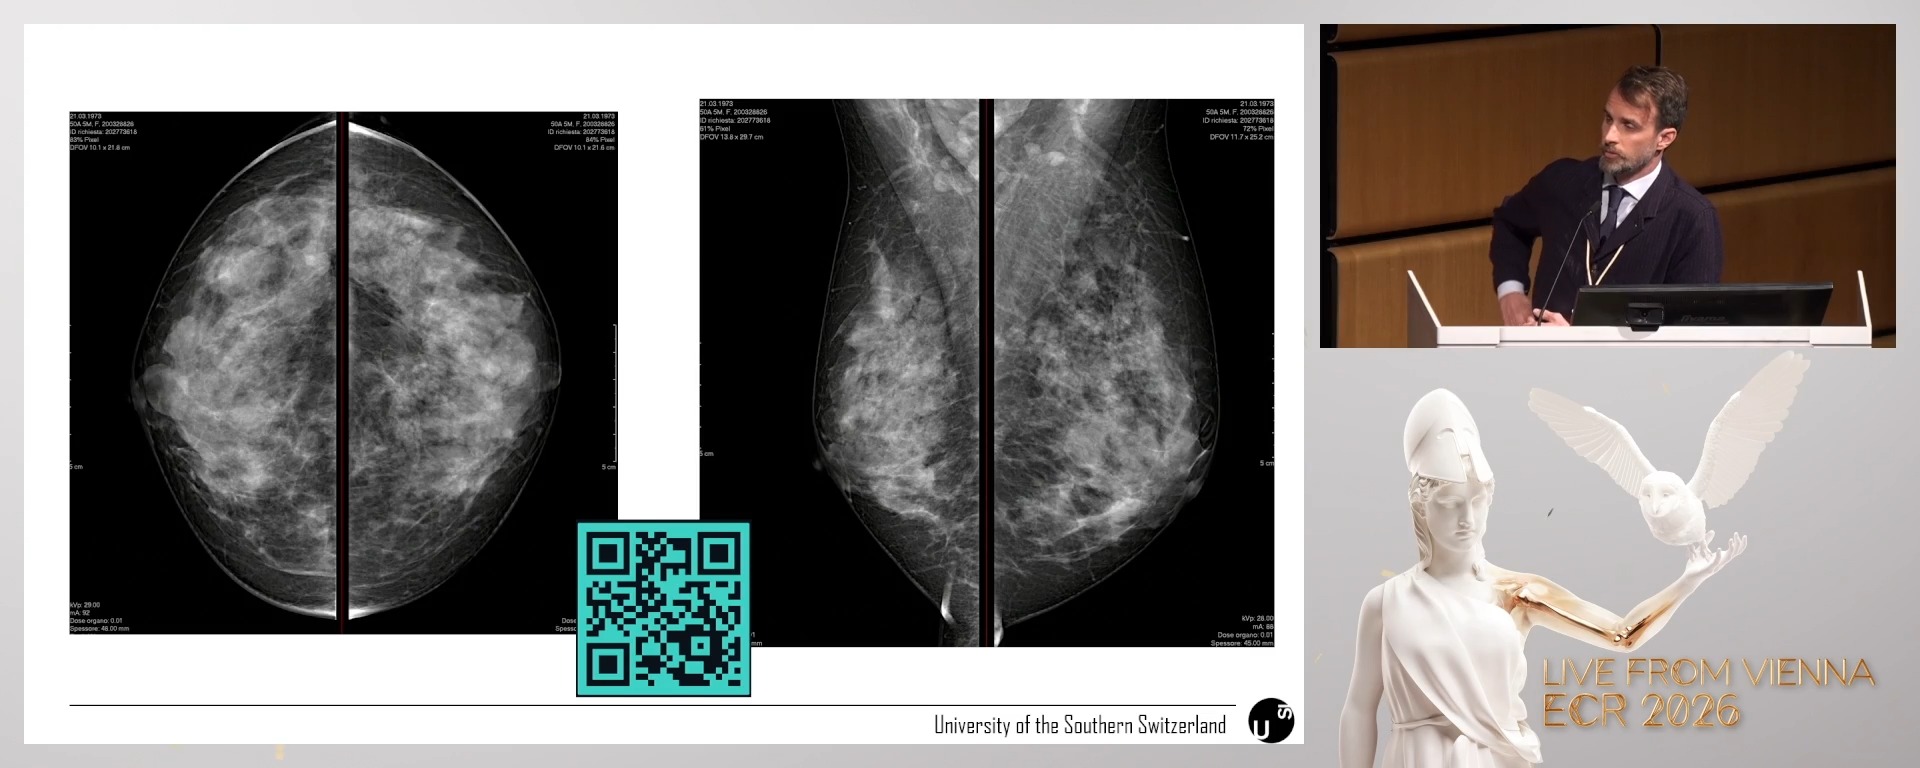

Breast lesions of uncertain malignant potential (B3 lesions): current strategies in assessment and management

Simone Schiaffino, Lugano / Switzerland

1. To describe the most frequent subtypes of B3 lesions encountered in clinical practice.

2. To recognise the challenges in selecting between active surveillance, vacuum-assisted excision, and surgery.

3. To consider the potential role of contrast-enhanced techniques in decision-making for B3 lesions.